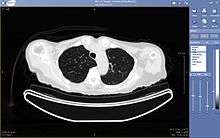

A picture archiving and communication system (PACS) is a medical imaging technology which provides economical storage and convenient access to images from multiple modalities (source machine types).[1] Electronic images and reports are transmitted digitally via PACS; this eliminates the need to manually file, retrieve, or transport film jackets. The universal format for PACS image storage and transfer is DICOM (Digital Imaging and Communications in Medicine). Non-image data, such as scanned documents, may be incorporated using consumer industry standard formats like PDF (Portable Document Format), once encapsulated in DICOM. A PACS consists of four major components: The imaging modalities such as X-ray plain film (PF), computed tomography (CT) and magnetic resonance imaging (MRI), a secured network for the transmission of patient information, workstations for interpreting and reviewing images, and archives for the storage and retrieval of images and reports. Combined with available and emerging web technology, PACS has the ability to deliver timely and efficient access to images, interpretations, and related data. PACS breaks down the physical and time barriers associated with traditional film-based image retrieval, distribution, and display.

Typically a PACS consists of a multitude of devices. The first step in typical PACS systems is the modality. Modalities are typically computed tomography (CT), ultrasound, nuclear medicine, positron emission tomography (PET), and magnetic resonance imaging (MRI). Depending on the facility's workflow most modalities send to a quality assurance (QA) workstation or sometimes called a PACS gateway. The QA workstation is a checkpoint to make sure patient demographics are correct as well as other important attributes of a study. If the study information is correct the images are passed to the archive for storage. The central storage device (archive) stores images and in some cases reports, measurements and other information that resides with the images. The next step in the PACS workflow is the reading workstations. The reading workstation is where the radiologist reviews the patient's study and formulates their diagnosis. Normally tied to the reading workstation is a reporting package that assists the radiologist with dictating the final report. Reporting software is optional and there are various ways in which doctors prefer to dictate their report. Ancillary to the workflow mentioned, there is normally CD/DVD authoring software used to burn patient studies for distribution to patients or referring physicians. The diagram above shows a typical workflow in most imaging centers and hospitals. Note that this section does not cover integration to a Radiology Information System, Hospital Information System and other such front-end system that relates to the PACS workflow.

More and more PACS include web-based interfaces to utilize the internet or a Wide Area Network as their means of communication, usually via VPN (Virtual Private Network) or SSL (Secure Sockets Layer). The clients side software may use ActiveX, JavaScript and/or a Java Applet. More robust PACS clients are full applications which can utilize the full resources of the computer they are executing on and are unaffected by the frequent unattended Web Browser and Java updates. As the need for distribution of images and reports becomes more widespread there is a push for PACS systems to support DICOM part 18 of the DICOM standard. Web Access to DICOM Objects (WADO) creates the necessary standard to expose images and reports over the web through truly portable medium. Without stepping outside the focus of the PACS architecture, WADO becomes the solution to cross platform capability and can increase the distribution of images and reports to referring physicians and patients.